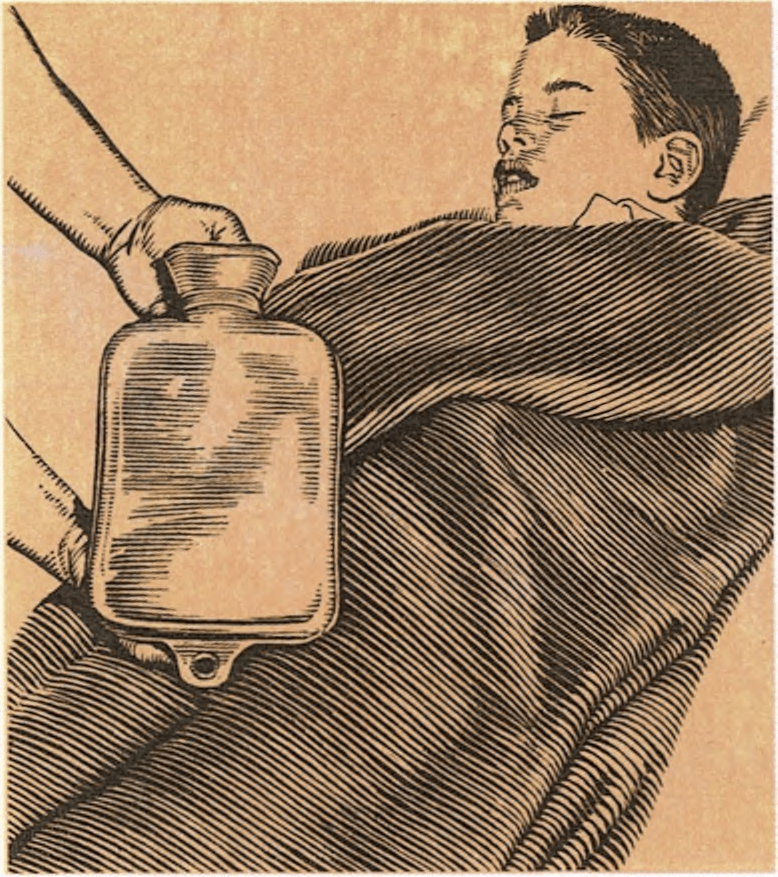

Si un niño tiene conmoción, se le tenderá sobre el suelo o sobre una cama. Si ha perdido mucha sangre, se le levantarán un poco los pies. Se debe procurar que no se enfríe, pero tampoco pecar por exceso y abrigarlo demasiado. Una manta debería bastarle. Si al tocarlo, parece que está demasiado frío, se calentará artificialmente con una botella de agua caliente o una esterilla eléctrica, procurando no quemarlo.